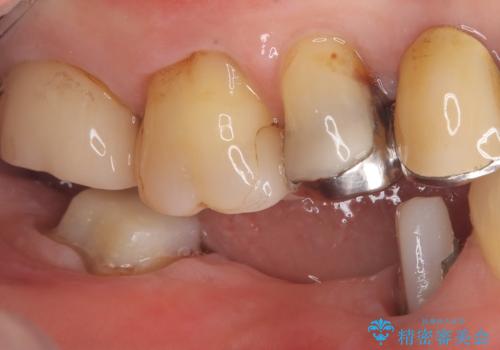

- 主訴:つい先日入れたセラミック(ジルコニア)ブリッジが奥歯部分で割れた。いつも同じ場所で壊れる。これで3度目。

セラミックに比べ、割れづらい金属(ゴールドでのブリッジのやり替えとなりました。

セラミックに比べ、破折リスクの少ない金属を使用したブリッジでのやり替えとなりました。

右下5番は支台歯CR築造を行っています。